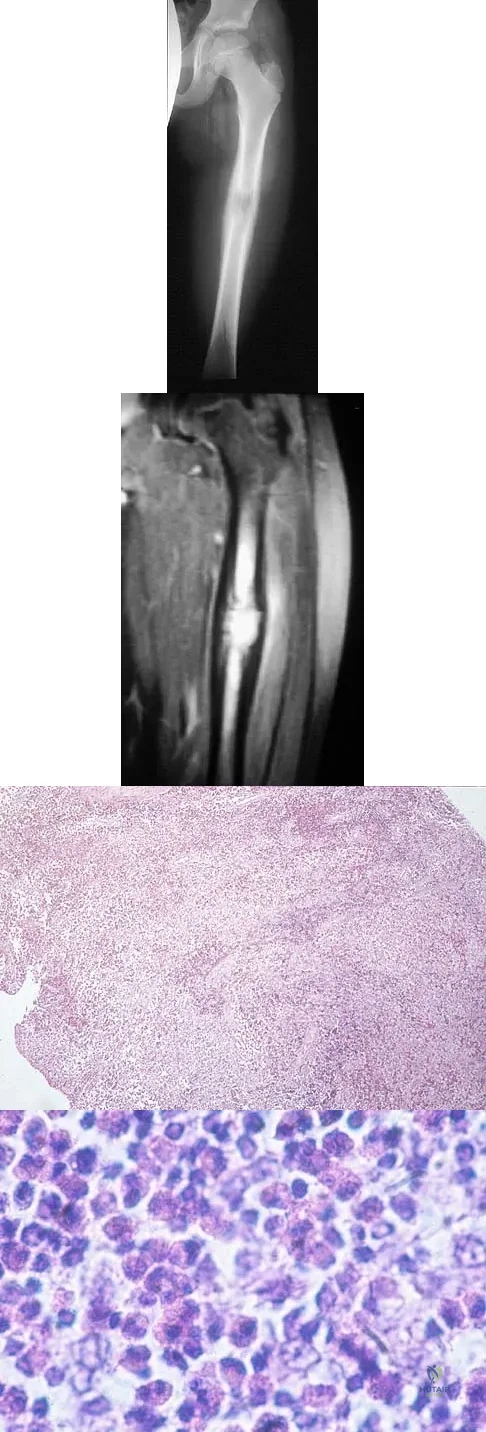

Question 87

A 10-year-boy has had thigh pain for the past several months. He denies any history of trauma. Examination reveals no soft-tissue mass, and mild tenderness. Figures 33a and 33b show the plain radiograph and MRI scan, and the biopsy specimens are shown in Figures 33c and 33d. What is the most likely diagnosis?

Explanation